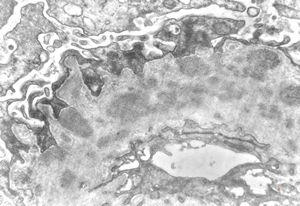

M,22y. | type II membranoproliferative glomerulonephritis